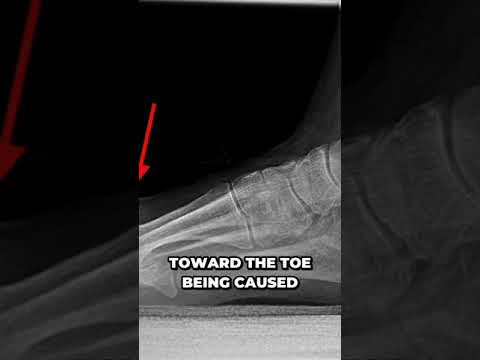

Shocking Arthritis Cyst Uncovered on Big Toe Joint @DrNailNipper 1

Shocking Arthritis Cyst Uncovered on Big Toe Joint @DrNailNipper